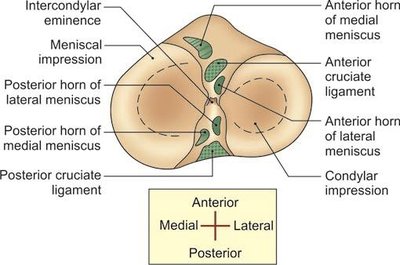

Menisci: Fibrocartilaginous structures that divide the joint cavity and aid in shock absorption.

Anterior and posterior cruciate ligaments: Prevent anterior and posterior displacement of the tibia.

Medial and lateral meniscus: Shock absorption and joint congruency.

Transverse ligament: Connects the menisci.

Flexion and extension occur in the upper compartment; rotation occurs in the lower (meniscotibial) compartment.